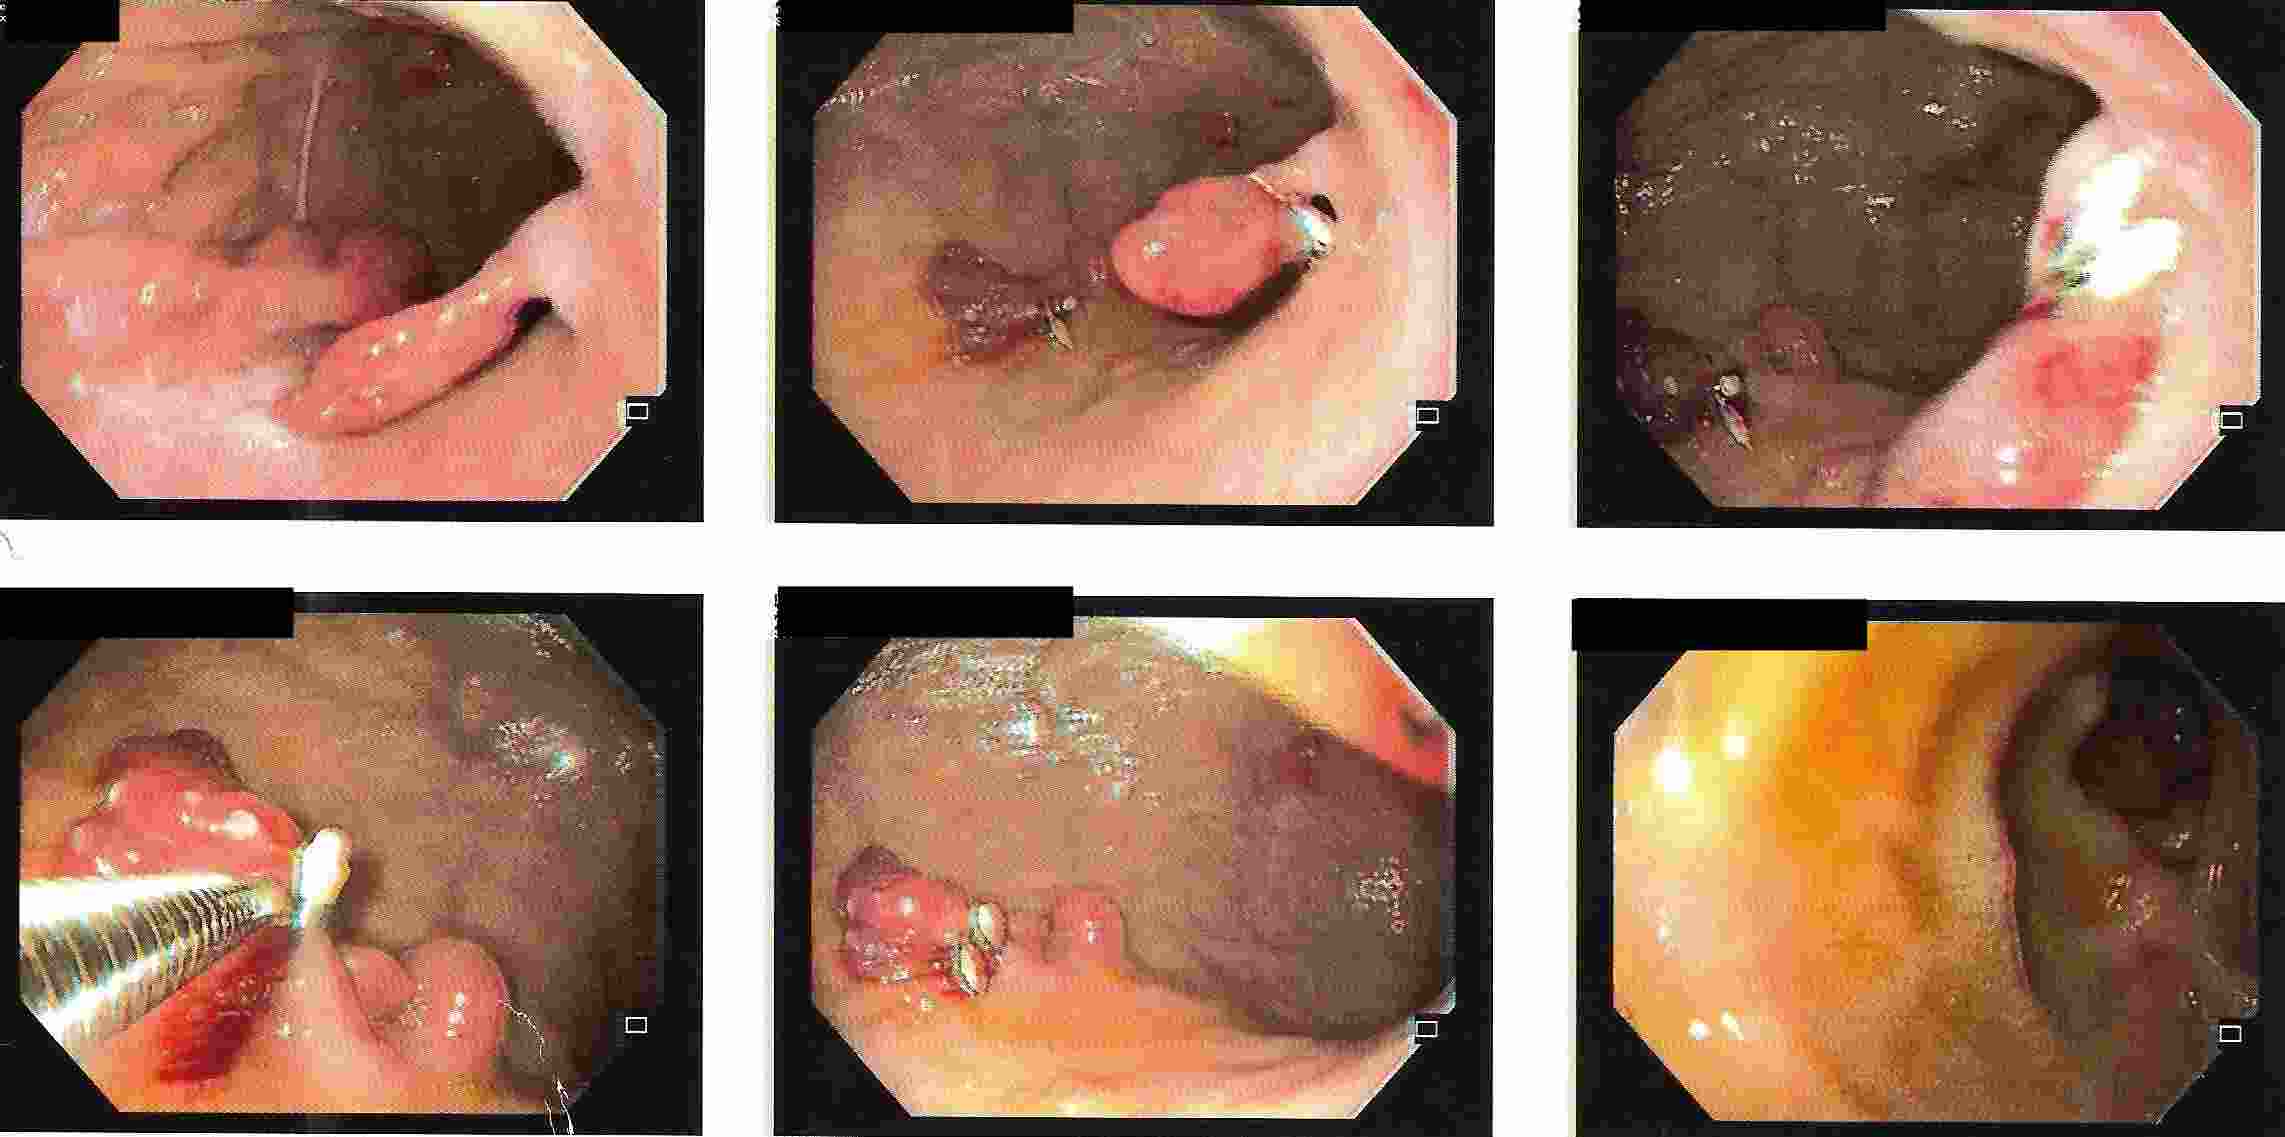

Tumours of the Stomach

Polyps of the Stomach